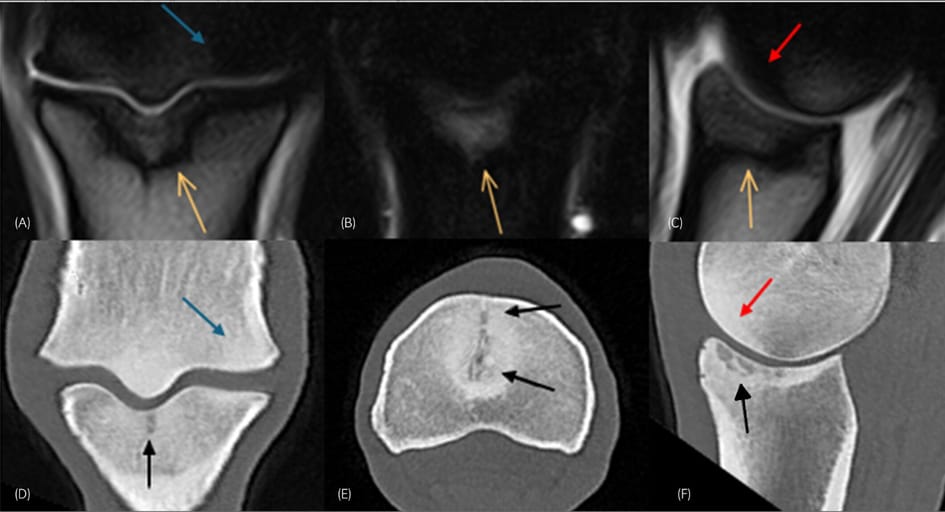

Frontal T2*W gradient echo (GRE) (A) and short tau inversion recovery (STIR) (B) and sagittal T2*W GRE magnetic resonance images (C) and frontal (D), transverse (E) and sagittal (F) computed tomographic (CT) reconstructions of the right forelimb of a 12-year-old showjumper (Table 1, Horse 1). Medial is to the right. There is hyperintense signal surrounded by a rim of low signal intensity in T2*W GRE images and hyperintense signal in the STIR image in the dorsal ¾ of the sagittal groove of the proximal phalanx, extending into the trabecular bone (orange arrows). In CT images there are hypoattenuating zones in the subchondral bone of the sagittal groove with an obvious hypoattenuating line dorsally (black arrows). Note also the diffuse hypointense signal/hyperattenuation in the dorsal aspect of the medial condyle (blue arrows) and the sagittal ridge (red arrows).

In 16 lame limbs, the primary lesion was in the proximal phalanx, especially the sagittal groove, showing extensive STIR hyperintensity with corresponding but more localized hypoattenuation on CT. In five limbs, metacarpal condyle lesions (including incomplete fractures and resorption) were best detected via CT; some were missed on MRI. In nine limbs, lesions in multiple areas contributed to pain. In one case, a proximal sesamoid bone and palmar ligament lesion was primary. CT proved more sensitive to subchondral bone resorption, while MRI was superior for detecting bone oedema and soft tissue abnormalities. Contralateral limbs often showed milder, subclinical versions of lesions. Contrast arthrography identified cartilage defects in 7 of 13 limbs imaged with contrast.